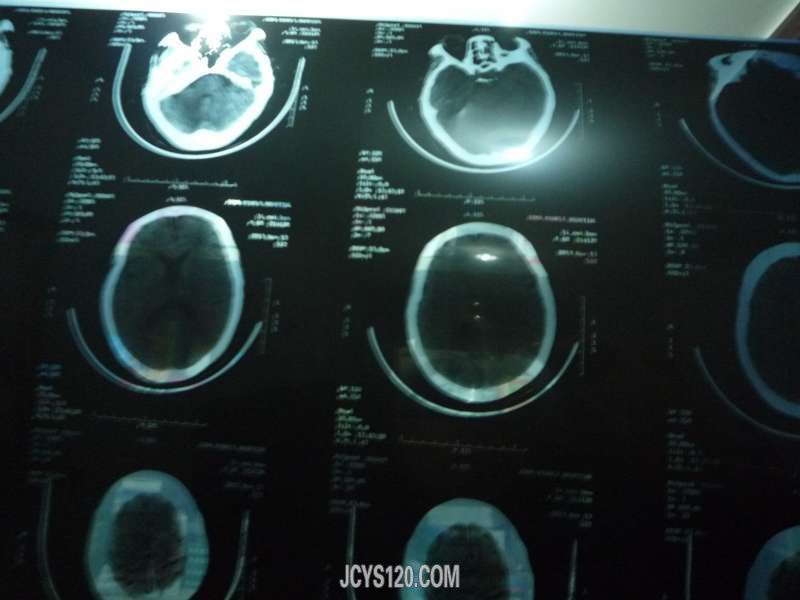

病史简要:患者李兰,女 60岁 主诉:胸腹部不适2小时 现病史:患者于2个小时前在l路上溜达突然出现胸腹部难受不适,伴有轻微头晕头痛,无恶心呕吐,无大小便异常,被邻居发现送回家,叫我速去就诊。(患者这段时间血压不稳定忽高忽低,最高180|120 ,在家口服尼福达降压,早晨7点口服一粒尼福达患者自述口服尼福达3小时后都会感觉难受不舒服,以前都是口服利血平,最近降压不理想换成尼福达) 既往史:高血压6年,(150|100),最高180|120 ,无糖尿病,无冠心病病史,否认药物食物过敏史 家族史:无家族遗传病史 查体:患者精神不佳,痛苦病容,脸色黄,血压140|85,心率89次每分钟,体重 156斤身高1米6,颈部无抵抗,全身皮肤无出血点,无黄染,全身淋巴无肿大,双肺呼吸音正常,双侧瞳孔等大等圆对光反射存在,气管居中,甲状腺未扪及,胸廓对称无畸形,心脏不大,心率89次,率齐,未闻及病理性杂音,腹部隆起(脂肪厚)无压疼及反跳痛,无肌紧张,无气过水声,肠鸣音正常,肝脾未触及,双下肢无水肿,生理反射存在病例反射未引出,左右肌力正常。 我仔细询问患者那里难受,患者一直在指着胸腹部包括肝胆区,说不上的感觉就是胀堵感觉(患者原话)大约持续1个半小时感觉逐渐减轻